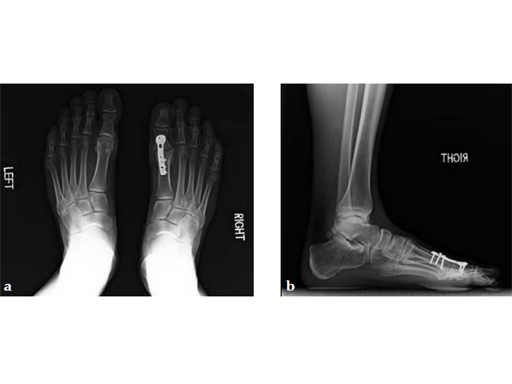

Case 8: VA -locking X-plate

A 38-year-old man fell from a 7-foot height while at work. The patient was seen at an urgent care facility and diagnosed with an ankle sprain. He was placed in a stirrup brace and instructed to bear weight as tolerated.

Case provided by Michael Castro, Scottsdale, Arizona

After 4 months the patient presented for a second opinion. His complaint was pain to the lateral column and subtalar joint. The preoperative lateral x-ray is notable for a malunited talar neck fracture with subluxation of the subtalar joint. The disproportion of the medial and lateral columns and a cavovarus position of the foot are seen on both the AP and lateral views. The degenerative changes at both the talonavicular and subtalar joints are significant.

The patient was treated with arthrodesis of the talonavicular and subtalar joints. The compression/ distraction device was used to restore the length of the medial column. The articular surface of the subtalar joint was prepared arthroscopically. The talonavicular joint was debrided then packed with a tricalcium matrix. Length was maintained using a locking X-plate. The subtalar joint was then fixed with a 6.5 mm headless compression screw.

The patient returned to work 3 months after surgery. He wears an ankle brace when on uneven surfaces. His lateral column and subtalar pain have resolved.